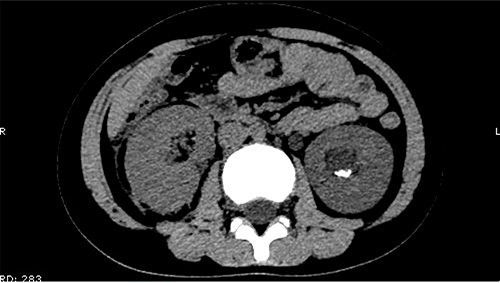

On 25 February, the patient complained of left back pain, nausea and vomiting. A further CT scan showed some irregular high-density shadows persisted in the left renal pelvis (Fig. 3) and an irregular high-density shadow was present in the left upper ureter (Fig. 4); furthermore, hydronephrosis was apparent in the left renal pelvis. There were no abnormalities in the bladder.

An irregular high-density shadow was present in the left upper ureter.